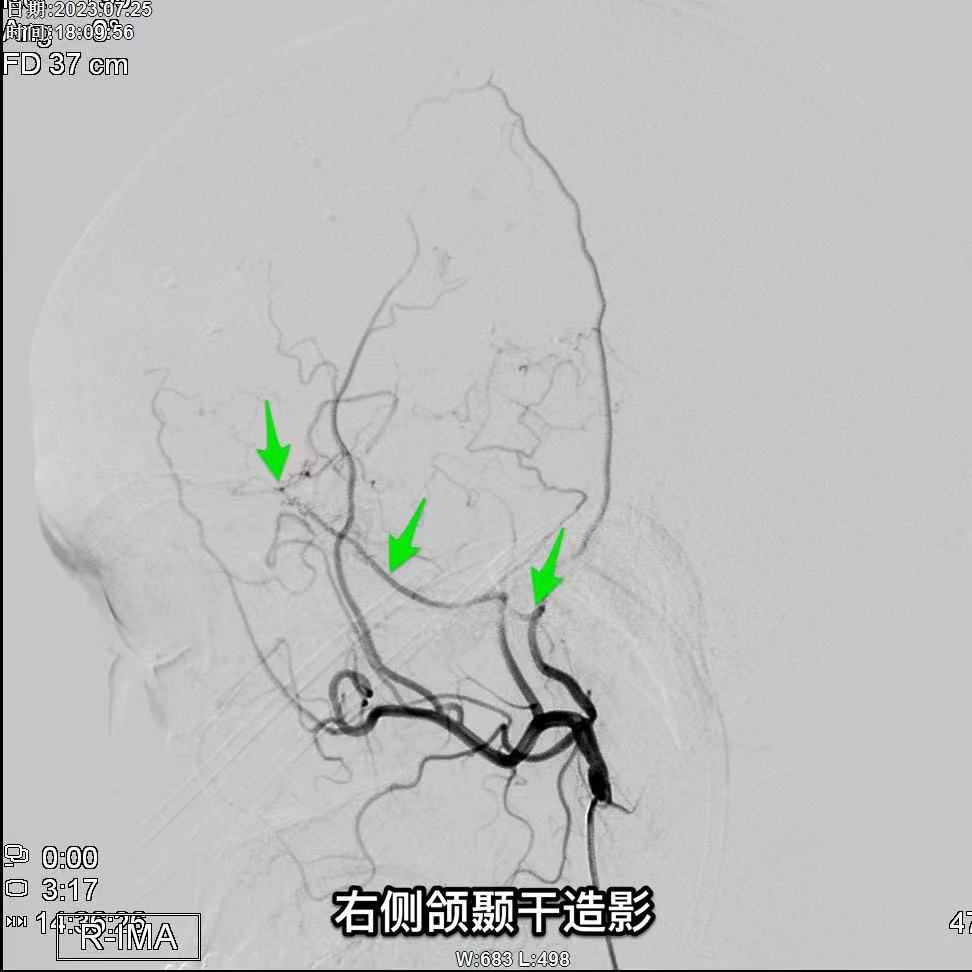

昆明三博2023:颞浅动脉一大脑中动脉M3吻合术